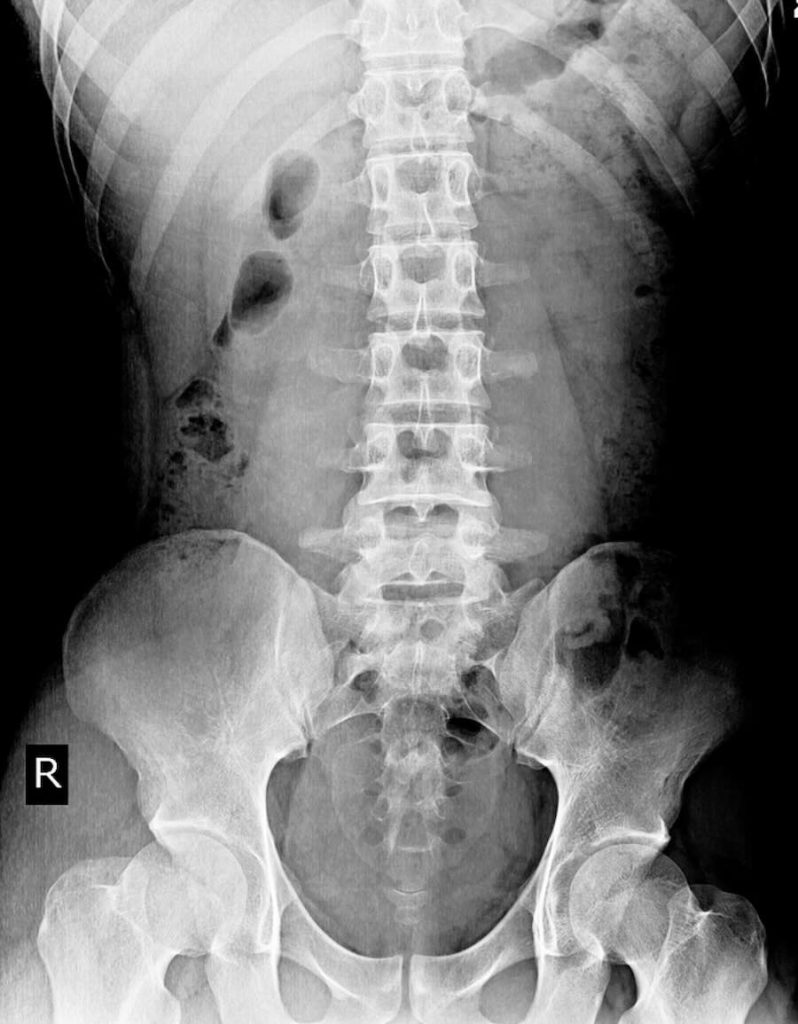

In some cases—especially with long-standing pain, previous trauma, or suspected structural changes—we may recommend digital spinal x-rays. These help us:

• See the alignment and curves of your spine

• Assess disc spaces and arthritic changes

• Identify areas of increased stress or instability

If we suspect a more serious disc or nerve issue that requires advanced imaging, we’ll coordinate with your medical doctor for MRI or specialist referral as needed.